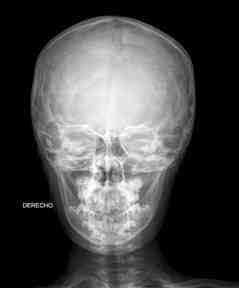

- Prueba: Rx de cráneo frente y perfil o cavum.

- Frente: Decúbito supino con un delantal plomado sobre el cuerpo. La inmovilización del cráneo variará en función también de lo movido que sea el niño (sujetando la con guante plomado o con dos almohadillas radiotransparentes a los lados de la cabeza, procurando siempre acercar la barbilla al pecho).